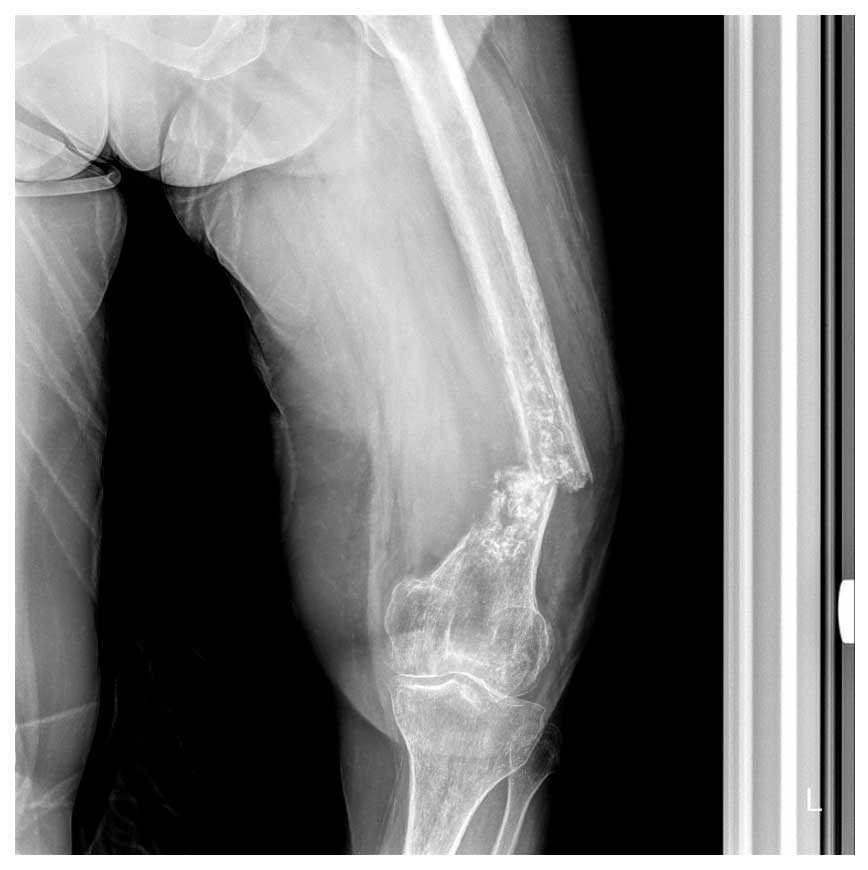

Ameliyat Öncesi: Röntgende distal femurda düzensiz kalsifikasyon, korteks destrüksiyonu ve deplase fraktür görülmekte.